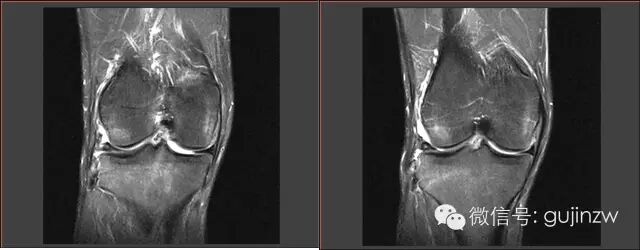

半月板损伤MRI

MRI正常解剖——外侧

内侧

MRI常见征象

• 直接诊断半月板损伤:3度损伤,半月板形态异常,半月板与关节囊分离。

• 征象:蝴蝶结缺失征,多蝴蝶结征,双后叉征。

3度损伤

半月板形体异常、与关节囊分离